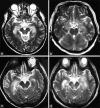

Figures